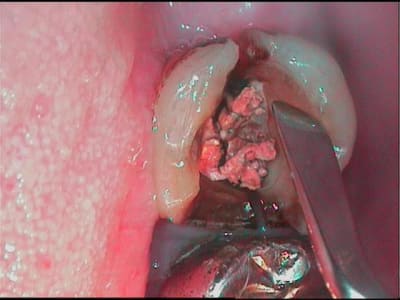

vu en urgence ce matin un patient avec fracture MOD sur sa 17.

Les 2 parties de la dent étant bien mobiles, j'ai procédé à l'extraction des deux morceaux et au curetage du tissu de granulation.

ci joint les trophés...

merci de la précision mais comme tu peux le voir, il y avait un tissu de granulation inter radiculaire qui a bouffé un peu l'os.